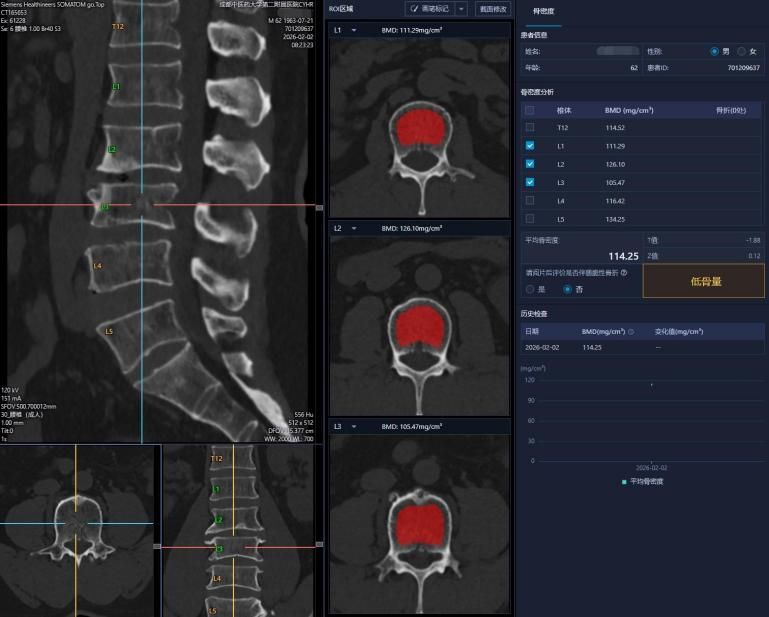

QCT,全稱(chēng)定量計(jì)算機(jī)斷層掃描。它與雙能X線吸收法(DXA)檢測(cè)骨密度一樣, 都是利用X射線進(jìn)行檢查的方法,而且與常規(guī)CT掃描類(lèi)似,通過(guò)專(zhuān)用的軟件和分析體模,能精確測(cè)量出骨骼(通常是腰椎)內(nèi)部真實(shí)的體積骨密度,單位mg/cm3。

3. 智能分析:掃描后,醫(yī)生在專(zhuān)用軟件上選取椎體中心的松質(zhì)骨區(qū)域,系統(tǒng)自動(dòng)對(duì)照體模計(jì)算出精確的骨密度值,并生成三維圖像和報(bào)告。

三、報(bào)告怎么看?關(guān)鍵讀懂“T值”

· -2.5 < T值 < -1.0:骨量減少(或稱(chēng)“低骨量”)。這是骨骼發(fā)出的“黃色預(yù)警”,需要開(kāi)始重視并干預(yù)。

· T值 ≤ -2.5:骨質(zhì)疏松癥。這是“紅色警報(bào)”,意味著骨折風(fēng)險(xiǎn)顯著增高,必須進(jìn)行規(guī)范治療。

此外,報(bào)告還有一個(gè) “Z值” ,它是與同年齡、同性別、同種族人群的比較,對(duì)兒童、青少年和絕經(jīng)前女性更有參考意義。

Z值>-2.0:處于正常同齡范圍;Z值≤-2.0:警報(bào)!低于正常同齡范圍。